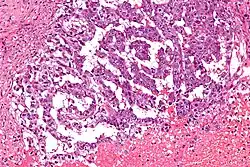

Tumor de células germinativas misto ao microscópio: carcinoma embrionário (à direita) e tumor do saco vitelino (à esquerda).

Tumor do seio endodérmico (TSE), tumor do saco vitelino ou ainda carcinoma embrionário infantil é um tumor de células germinativas maligno raro. Pode aparecer em um testículo ou em um ovário, raramente em ambos. É o câncer de testículo mais comum em crianças menores de 3 anos. Nessa faixa etária tem uma elevada sobrevivência e responde bem à quimioterapia. [1]

Por biópsia e microscopia. Secreta alfafetoproteína (AFP) que pode ser detectada em um exame de sangue. Em contraste com a forma pura que aparece nos bebês, os tumores do seio endodérmico dos adultos são frequentemente encontrados em combinação com outros tipos de tumor de células germinativas (tumor misto), especialmente com um teratoma ou um carcinoma embrionário.[2]